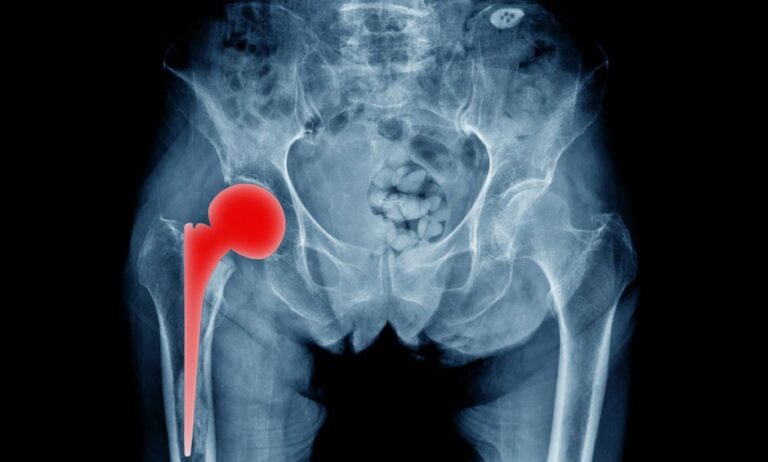

Η ολική αρθροπλαστική ισχίου είναι μια επέμβαση που κατά κύριο λόγο εφαρμόζεται ως τελική θεραπευτική λύση για την αντιμετώπιση της οστεοαρθρίτιδας του ισχίου. Η οστεοαρθρίτιδα